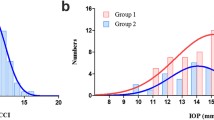

Figure 1 shows the frequency distribution of MvD, which was consistent with the distribution of the focal LC defects.